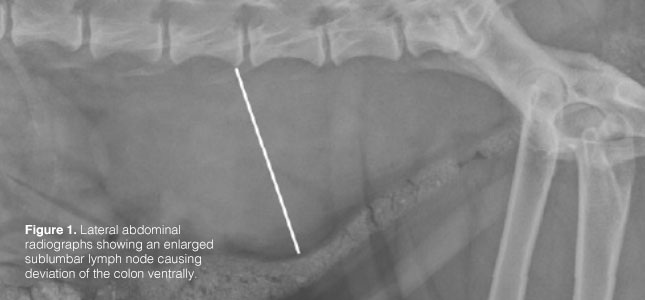

The reported rate of metastasis at the time of diagnosis ranges from 50-80%. Therefore, prior to surgery and other therapies, staging with three view chest x-rays and an abdominal ultrasound are recommended. The sublumbar lymph nodes are one of the most common sites for metastasis (Figure 1). This lymph center includes the medial iliac, hypogastric, and sacral lymph nodes and is located within the caudal abdomen and pelvis. More common distant metastatic sites include the spleen, liver, and lungs. Rarely, regional bone metastasis or direct extension of tumor from the sublumbar lymph nodes to the lumbar vertebrae can occur.